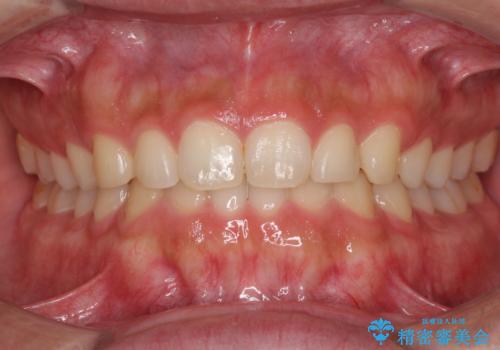

八重歯を治す 非抜歯のワイヤー矯正治療

- 左右の八重歯を気にして来院された患者様です。

ワイヤー装置でもマウスピースでも対応可能な歯列でしたが、マウスピース矯正は自己管理が煩わしいとのことでワイヤー矯正を選択されました。

八重歯である犬歯は歯根が長いため、上顎前歯が出っ歯になるリスクがあるため、必要に応じてアンカースクリューを用いて奥歯を後方に移動させる可能性をお伝えしました。

舌の突出癖により上下前歯が開咬となりましたが、舌のトレーニングと顎間ゴムの使用により、元々の被蓋関係に改善することができました。

アンカースクリューを用いて、出っ歯仕上がりを回避し、正中位置も改善することができました。